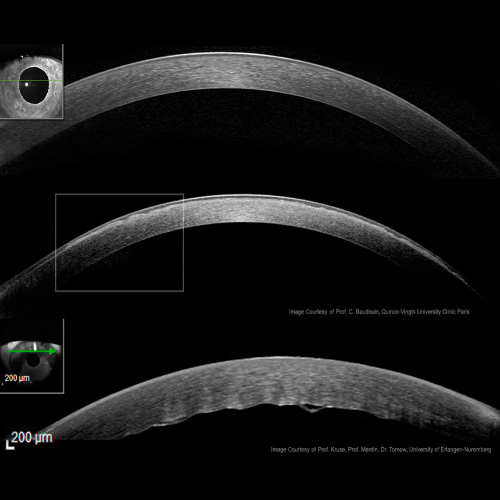

Estudia la anatomía y las capas de la córnea, además de las alteraciones ultraestructurales

Estudia los cambios producidos en la conjuntiva por efecto de la inflamación y neoplasias